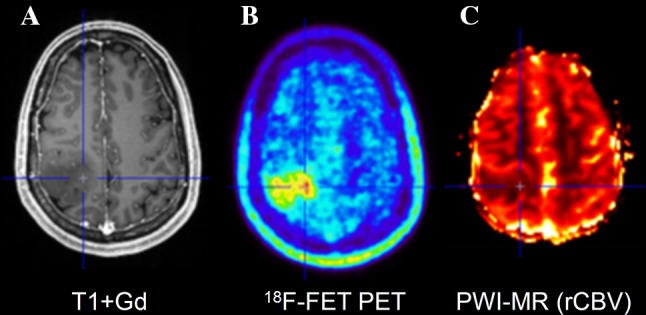

For PET, a number of studies have explored the spatial correlation of histopathological findings with amino acid uptake and provided evidence that the solid tumour mass of gliomas typically shows increased amino acid uptake and detects tumour extent more reliably than standard MRI [57–62] (Fig. 2). The improved delineation of tumor extent is one of the most important advances in brain tumor diagnostics provided by amino acid PET, but it has to be considered that a fraction of approx. 5% of all gliomas, especially low-grade gliomas, do not accumulate radiolabeled amino acids [35]. Nevertheless, amino acid PET is clearly superior to the standard MRI and the property of amino acid PET to detect tumour extent has been used in many studies for treatment planning, especially in tumor resection and radiation therapy [63–73]. In contrast, only a few studies have investigated the diagnostic value of PWI for the detection of brain tumour extent [74, 75]. Those studies observed elevated rCBV beyond the contrast-enhancing volume indicating that tumour infiltration might also be detected by PWI. A biopsy-controlled study reported that rCBV regionally correlates with both cell and microvessel density within gliomas [76]. Another biopsy-controlled study demonstrated that rCBV correlated with cell proliferation in high-grade gliomas but a correlation of rCBV with tumour cell density could not be confirmed [74]. These studies suggest that rCBV mapping allows only very limited conclusions with regard to tumor extension. While some earlier studies comparing amino acid uptake and rCBV observed similarities between MET uptake and rCBV abnormalities in gliomas [77, 78], more recent publications reported on considerably larger tumour volumes in amino acid PET than in rCBV maps and a poor spatial overlap [23, 79–82] (Figs. 3, 4; Table 1). Furthermore, rCBV mapping exhibited a lower lesion-to-brain contrast and a highly variable background noise as compared with amino acid PET [23, 79]. Another hybrid PET/MRI study reported that artifacts due to susceptibility differences between bone and air, iron accumulations, and blood degradation products hampered interpretation of the rCBV signal in the tumour area in 56% of the patients [80]. Thus, amino acid PET appears to be superior to rCBV mapping for the detection of the extent of cerebral gliomas and interpretation of rCBV maps appears to be more challenging than with amino acid PET.

Fig. 5.

Hybrid PET/MRI of patient with a glioblastoma WHO grade IV. Contrast-enhanced T1-weighted MR imaging (A) shows a small area with contrast enhancement in right parietal lobe and corresponding signal abnormality in the FLAIR image (B) which shows focal tracer uptake in FET PET (C) and correspondingly increased rCBV (D)